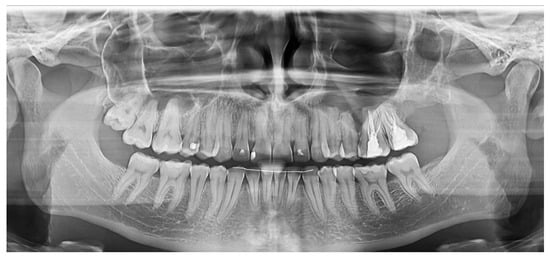

2.2.1. Case 1

2.2.2. Case 2

2.2.3. Case 3